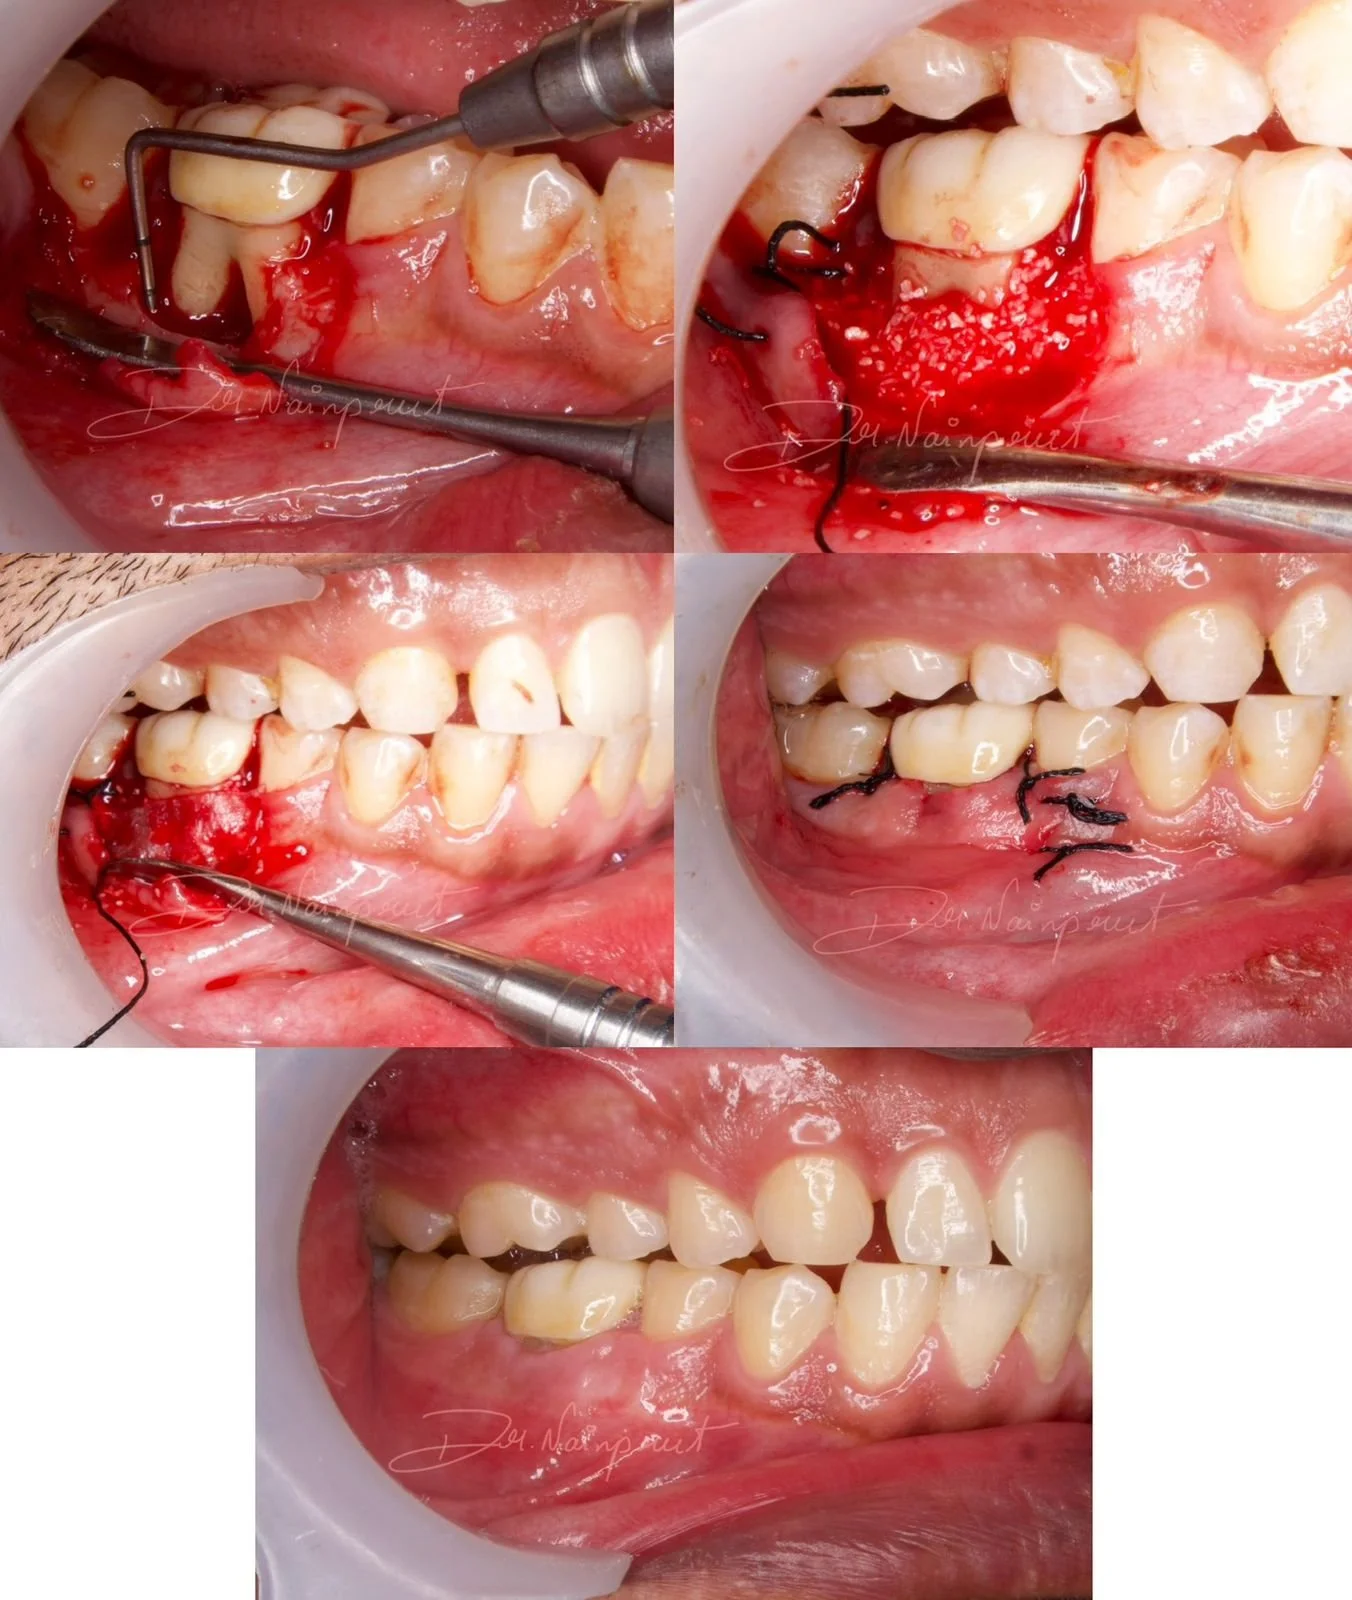

ROOT COVERAGE WITH CORONALLY ADVANCED FLAP

Surgery performed by Dr Poulami